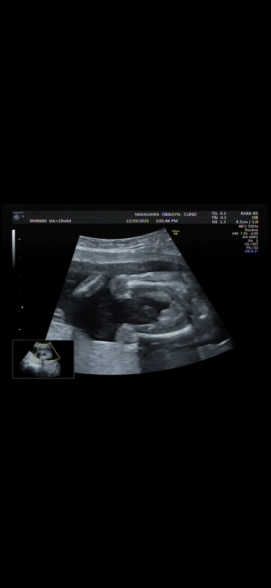

19週になりましたが、まだ性別がわかりません。 正月に家族とも話したいなーと思っているのですが 次の検診が年明けなので もし分かるのであれば教えて欲しいです!

へその緒が近くにあるのでわかりづらく、、

確定はできないのはわかっていますが多分どっちかでも知りたいです、、!

お腹の赤ちゃんの性別についてですね。

添付をしてくださった画像を拝見いたしました。

男の子のシンボルとなりそうなものがありそうに見えあたり、なさそうにも見えたりと、どちらかということもお返事がしにくい状況でした。